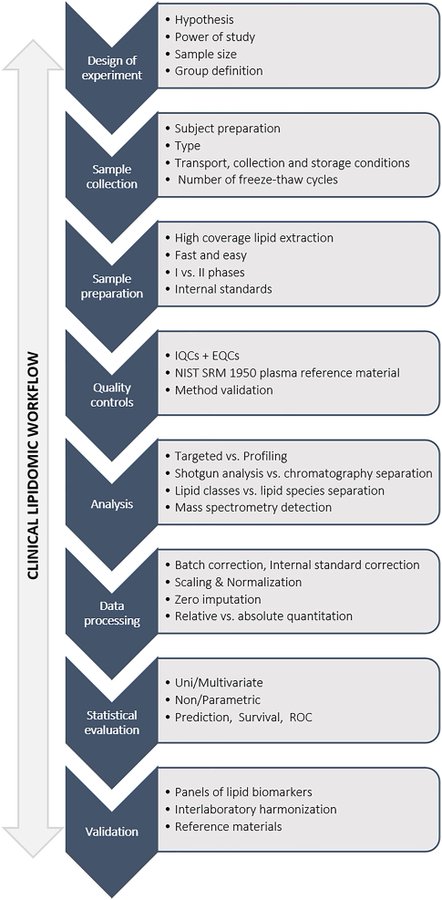

Dysregulation of Amino Acid, Lipid, and Acylpyruvate Metabolism in Idiopathic Intracranial Hypertension: A Non-targeted Case Control and Longitudinal Metabolomic Study.